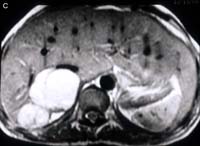

ตัวอย่างของ adrenal adenoma ดังรูปที่11

รูปที่11 ภาพเอกซเรย์คอมพิวเตอร์ (CT) ของผู้ป่วยหญิงที่มีอาการทางคลินิกเป็น Cushing syndrome แสดงก้อนที่ขาข้างหนึ่งของต่อมหมวกไตข้างซ้าย (2) ซึ่งผลทางพยาธิเป็น adenoma ข้างขวาปกติ (ลูกศร)(ได้รับภาพอภินันทนาการจาก พ.ญ.ลัดดาวัลย์ วัชระคุปต์)